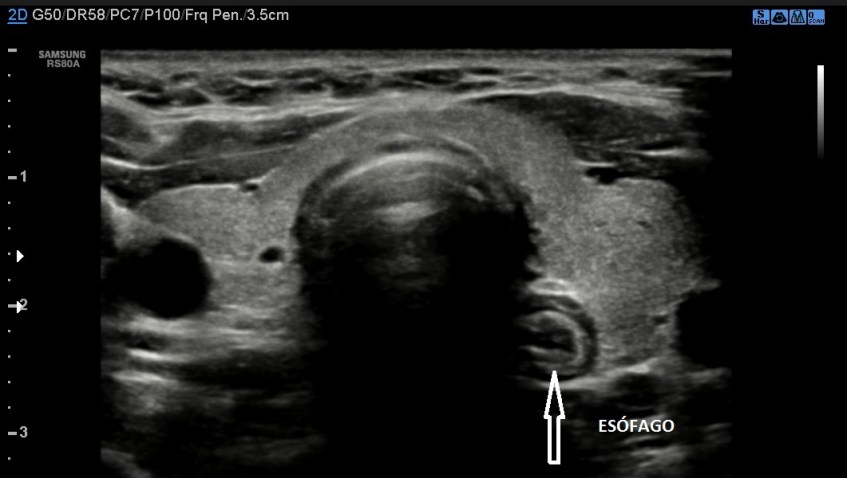

Imagen 6.El Esófago.

Esta estructura como muy bien sabes pertenece al sistema digestivo, teóricamente aparece siempre en la linea media según la anatomía, pero cuando hacemos el corte ecográfico axial del cuello para ver en transverso de ambos lóbulos aparece hacia la izquierda una estructura en forma de diana, que con la deglución se mueve, el Esófago. Tiene aspecto circular, hipoecogénico con círculos hiperecogénicos correspondiente a las capas de dicha estructura. Su presencia hace que el LTI sea ligeramente más pequeño, como curiosidad.

This structure as you know very well belongs to the digestive system, theoretically always appears in the middle line according to the anatomy, but when we make the axial ultrasonographic section of the neck to see in transverse of both lobes a target structure appears to the left, which with swallowing it moves, the esophagus. It has a circular, hypoechogenic appearance with hyperechogenic circles corresponding to the layers of said structure. Its presence makes the LTI slightly smaller, as a curiosity.